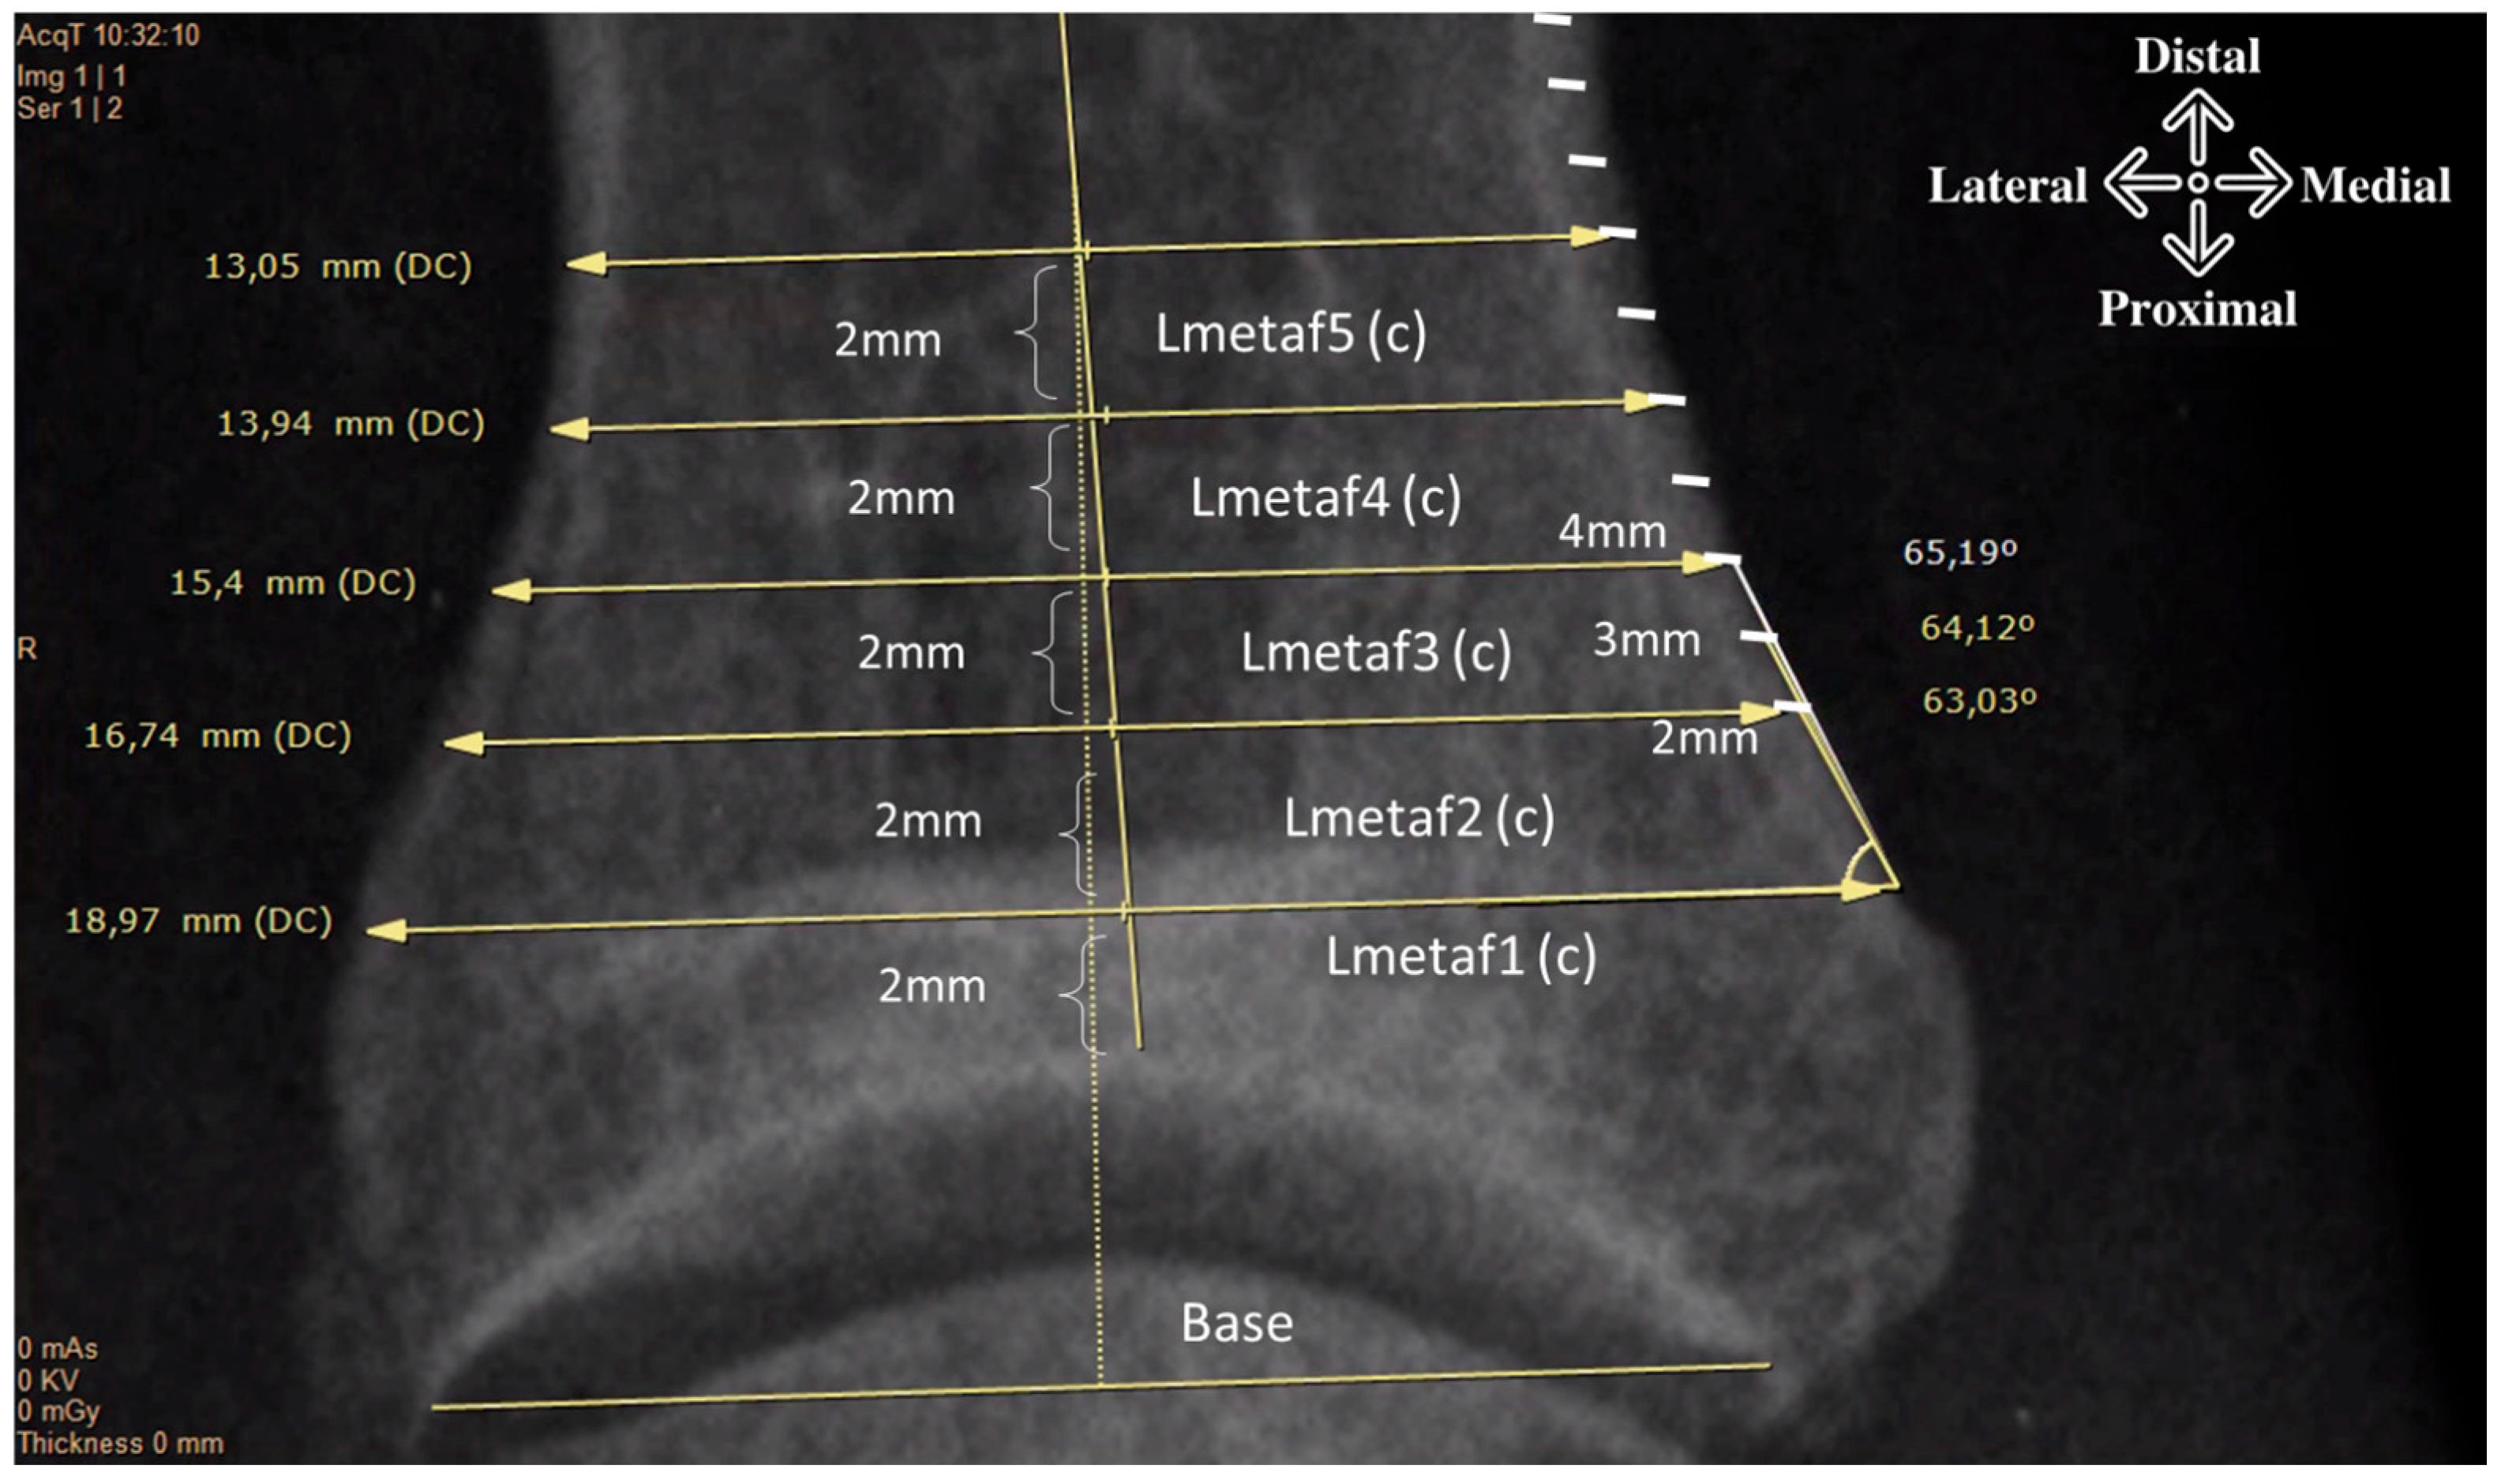

| Lbase, mm | 16.71 | 1.48 | 12.66 | 23.23 | Width of the base (c) |

| LMetaf1, (c), mm | 18.75 | 1.45 | 15.13 | 23.91 | |

| LMetaf2, (c), mm | 17.43 | 1.62 | 13.57 | 23.95 | |

| LMetaf3, (c), mm | 15.22 | 1.69 | 11.59 | 21.43 | |

| LMetaf4, (c), mm | 13.41 | 1.56 | 9.98 | 17.96 | |

| LMetaf5, (c), mm | 12.27 | 1.43 | 8.99 | 15.96 | |